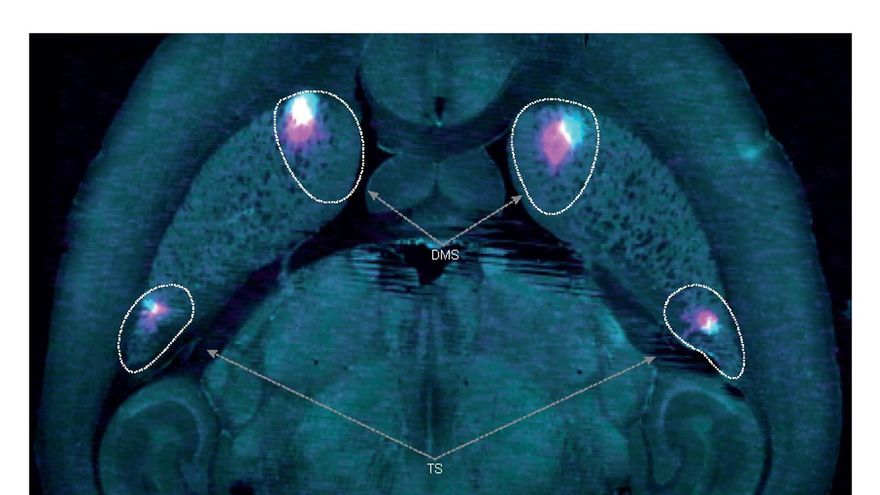

Los investigadores descubrieron una señal de dopamina (un neurotransmisor) en el cerebro que actúa como un tipo de señal didáctica diferente a la conocida hasta ahora.

Se sabía que las señales de dopamina en el cerebro forman errores de predicción de recompensa (EPR) que indican al individuo si una opción es mejor o peor de lo esperado (es el circuito que impulsa a los individuos a buscar placer).

En este nuevo estudio, los autores descubrieron que en paralelo a los errores de predicción de recompensa, hay una señal dopaminérgica adicional, denominada error de predicción de la acción (APE), que actualiza la frecuencia con que se realiza una acción.

Estas dos señales de enseñanza proporcionan a los individuos (en este caso ratones) dos formas distintas de aprender a hacer una elección, aprendiendo a elegir la opción más valiosa o la más frecuente, concluye el estudio.

Esta investigación también tiene implicaciones potenciales para el Parkinson, que se sabe que está causado por la muerte de neuronas dopaminérgicas del mesencéfalo, las relacionadas con el movimiento, que pueden ser responsables de la codificación del APE.